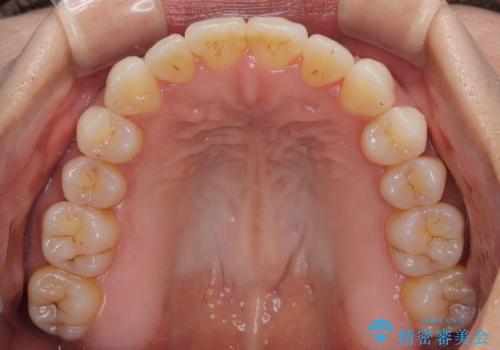

前歯のクロスバイト インビザラインによる矯正治療

- 上下のクロスバイトと前歯のデコボコを気にして来院された患者様です。

インビザラインを用い、IPR(歯と歯の間を削る)と歯列全体を拡大させることで、歯並びを整えていくこととしました。

インビザライン特有の、治療後半に奥歯が咬み合わないという事象が長引きました。

咬み合わないときの対処方法は色々とありますが、ゴムかけなどを活用して噛めるようにしました。